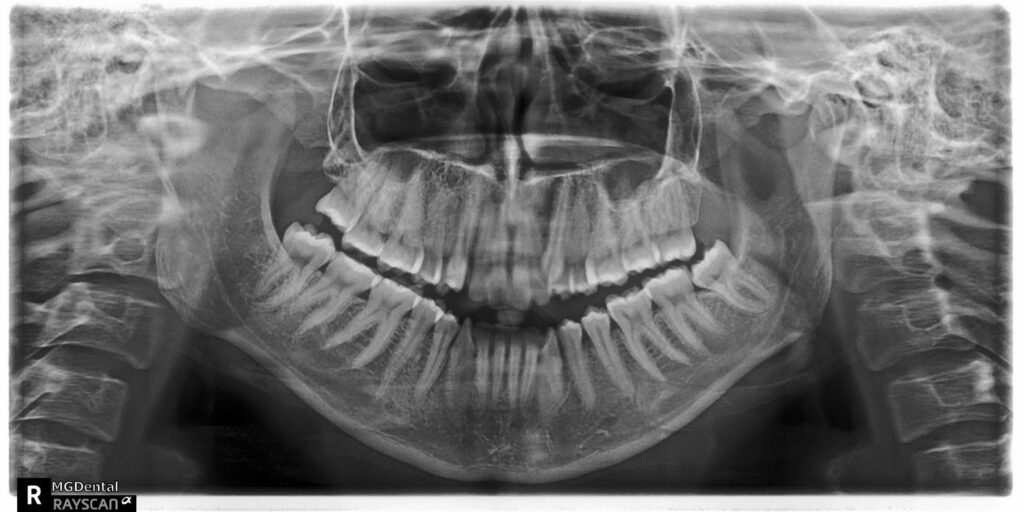

A 27-year-old female patient presented with class III malocclusion, 15 mm crowding in the upper arch, an anterior open bite, a lateral crossbite, and a total ABO score of 29. Her facial profile was straight with a retrusive maxilla, and the upper and lower incisors were retroclined. An extreme lack of midface support was also noted, and the constricted dental arches resulted in a poor smile width and dark buccal corridors. No myofunctional investigations were performed at the time, as they were initially considered unnecessary.

The treatment began in 2017. Given the patient’s preference for less visible brackets, Damon Clear brackets were selected. High torque upper cuspids and low torque upper incisors were chosen to offer the best torque control for upper arch development. For the lower arch, there were no alternative bracket configurations available. Bite turbos were applied to the upper second molars.